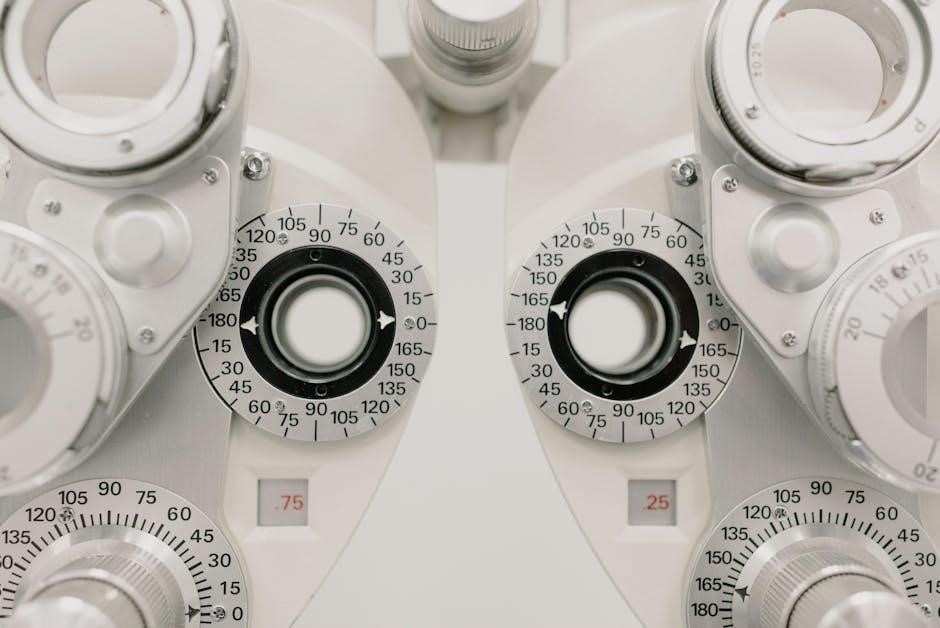

II. Optic Nerve (Vision) – Visual Acuity & Fields

Evaluating the optic nerve (CN II) begins with assessing visual acuity, typically using a Snellen chart at a standard distance (20 feet). Each eye is tested individually, both with and without corrective lenses, documenting the best-corrected visual acuity.

PDF guides detail the importance of accurately recording the results, such as 20/20, 20/30, or worse. Following acuity testing, visual fields are assessed by confrontation, comparing the patient’s peripheral vision to the examiner’s.

Formal perimetry can be used for more precise field mapping. PDF resources often illustrate how to perform accurate confrontation testing, emphasizing the importance of consistent stimulus presentation. Defects in the visual field, like scotomas or hemianopsia, can indicate optic nerve damage or lesions along the visual pathway. Careful documentation of any field deficits is crucial for diagnosis and monitoring.